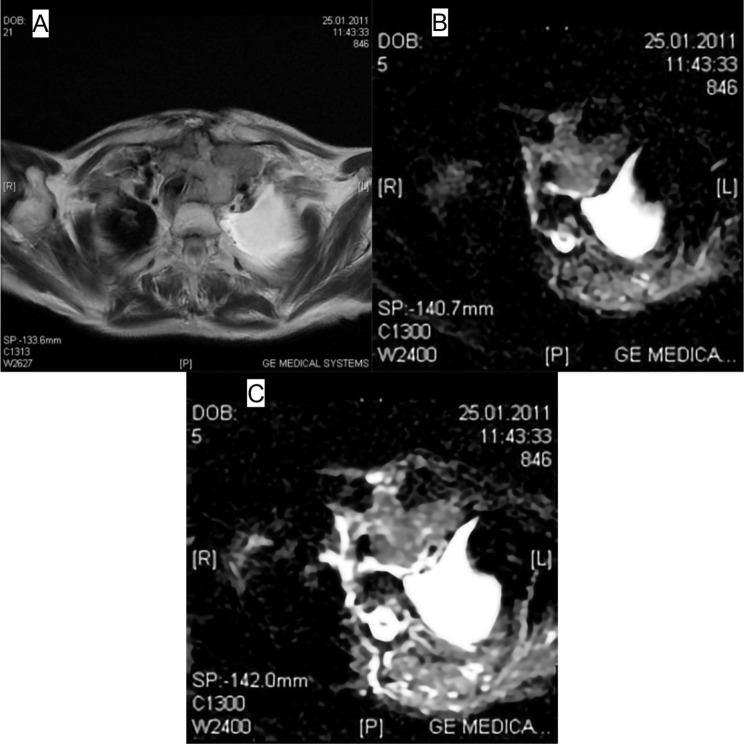

Materials and methods: Patients presenting with a preoperative diagnosis of nodular goiter or multinodular goiter were included in this study. These patients underwent neck MRI examinations, and their cases were analyzed retrospectively. A total of 26 patients were included in the study. A total of 46 nodules meeting the study criteria were examined. Measurements were performed on Apparent Diffusion Coefficient (ADC) maps of patients at two different b values (b 500 s/mm² and b 800 s/mm²), and the results were compared with histopathological findings.

Results: Out of a total of 46 nodules, 37 were identified as benign, and 9 as malignant based on histopathological analysis. The mean ADC value at b 500 was lower in malignant nodules (1259.65 ± 328.13) compared to benign nodules (19037.48 ± 472.74). Similarly, the mean ADC value at b 800 was lower in malignant nodules (1081.72 ± 200.23) compared to benign nodules (1610.44 ± 418.06). When a cut-off value of 1.1 × 10- 3 was accepted for the differentiation of pathology, the sensitivity for distinguishing pathology with ADC values at b 500 was 83.3%, with a specificity of 90.0%, and for ADC values at b 800, the sensitivity was 71.4%, with a specificity of 89.7%.

Conclusion: DW-MRI without the need for contrast agent administration is a useful method in the differentiation of benign-malignant thyroid nodules.